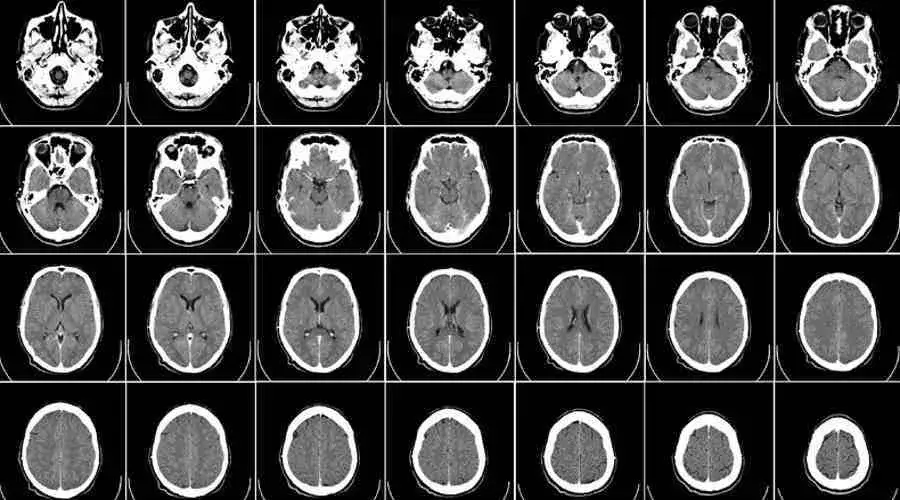

Rezonans magnetyczny głowy to niezwykle precyzyjna technika obrazowania, która wykorzystuje silne pole magnetyczne i fale radiowe do tworzenia szczegółowych obrazów struktur anatomicznych mózgu. Na obrazach MRI lekarz jest w stanie zwizualizować z wysoką dokładnością tkanki miękkie, naczynia krwionośne, płyn mózgowo-rdzeniowy oraz wszelkie zmiany strukturalne, takie jak guzy, torbiele, obszary uszkodzeń po udarach czy ogniska demielinizacyjne. Ważne jest, aby zrozumieć, że MRI pokazuje nam fizyczną architekturę mózgu. Nie jest to jednak narzędzie, które bezpośrednio "widzi" nasze myśli, emocje, wspomnienia czy samą chorobę psychiczną w sensie jej psychologicznego podłoża. Widzimy natomiast zmiany strukturalne, które mogą być z nimi skorelowane.Dlaczego psychiatra może skierować Cię na rezonans? Kluczowa rola diagnostyki różnicowej

Głównym powodem, dla którego psychiatra może zlecić rezonans magnetyczny głowy, jest diagnostyka różnicowa. Oznacza to, że celem badania jest wykluczenie organicznych, czyli fizycznych przyczyn objawów psychicznych, które mogą łudząco przypominać zaburzenia psychiczne. W mojej praktyce często spotykam się z sytuacjami, gdzie pacjent zgłasza objawy takie jak zmiany nastroju, problemy z pamięcią czy zaburzenia osobowości, które na pierwszy rzut oka sugerują chorobę psychiczną. Jednakże, bez wykluczenia podłoża neurologicznego, diagnoza psychiatryczna może być niepełna lub błędna. MRI pozwala nam upewnić się, że objawy nie są spowodowane przez:

Tutaj muszę być bardzo stanowcza: nie, skan MRI zazwyczaj nie jest narzędziem do jednoznacznego potwierdzania większości chorób psychicznych. W przeciwieństwie do złamania kości czy guza, które są wyraźnie widoczne na obrazie, zaburzenia psychiczne, takie jak depresja, schizofrenia czy zaburzenia lękowe, nie mają "markera" w postaci konkretnej, łatwo rozpoznawalnej zmiany strukturalnej, która byłaby widoczna w rutynowym badaniu MRI i stanowiła podstawę do postawienia diagnozy. Rezonans magnetyczny jest narzędziem pomocniczym, niezwykle cennym w procesie diagnostycznym, ale nie jest ostateczną wyrocznią. Diagnoza psychiatryczna opiera się przede wszystkim na wywiadzie klinicznym, obserwacji objawów i kryteriach diagnostycznych.